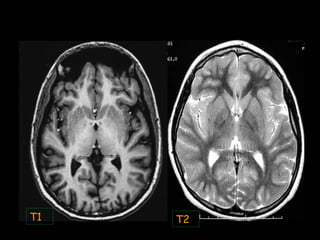

SE T1 Aspect en échelle de gris SE T2

Blanc

(Hypersignal)

Graisse LCS

S Blanche Graisse

S Grise

S Grise Gris S Blanche

LCS

Calcium

Air

Noir

(Hyposignal)

Imagerie par Résonance MagnétiqueImagerie par Résonance Magnétique

T1 T2